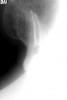

zybnaya feya Опубликовано 31 января, 2011 Поделиться Опубликовано 31 января, 2011 (изменено) Сегодня пришла такая пульпитная красотка. http://s41.radikal.ru/i092/1101/a9/f870fab317c3.jpg Я пока рабочую длину померяла,влезла протейпером,ломанула его мигом)) Удалось обойти обломок,достать не получилось. Думаю что в МБ была дельта крупная или МБ2 отходил,тейпер в нее и врезался Устья нашла только три. МБ щелевидное. http://s52.radikal.ru/i138/1101/c5/1ecde9d5ef1d.jpghttp://s47.radikal.ru/i117/1101/97/a14cdbda90c5.jpg получилось так обтурировать(АН+,термафил) http://s41.radikal.ru/i094/1101/3e/bf6508bd65d6.jpg Изменено 31 января, 2011 пользователем zybnaya feya Ссылка на комментарий